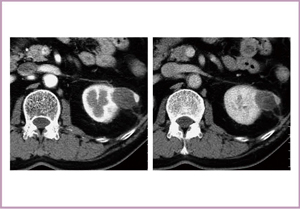

●症例1:46歳,男性,右腎癌

右腎の上局に,早期に造影効果を示す腫瘤が認められ,後期では抜けている(図6)。凍結治療時,MRIでは明瞭な低信号域として氷が描出される(図7)。MRIでは多方向からの撮像が可能で,完全に氷が腫瘍をカバーしているかを確認して治療を進めていくことができる。3週間後の造影CTでは,凍結部位の内部に造影効果が認められる特徴的な所見が得られた。RFの場合は,ほぼ完全に消えてしまうが,凍結治療では造影効果がいつまでも残る場合があり,その評価は今後の課題である。8か月後には,瘢痕組織が収縮していることが確認された。

図6 症例1:46歳,男性,右腎癌

右腎の上局に,早期に造影効果を示す腫瘤が認められ(a),後期では抜けている(c)。